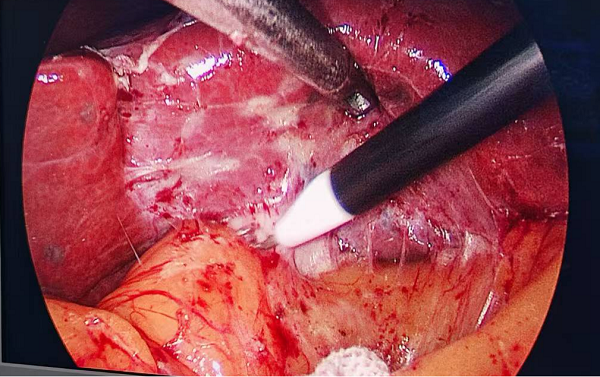

因反复炎症反应,患者腹腔内严重粘连,极大增加了手术的难度与风险。

术中见患者腹腔内严重粘连